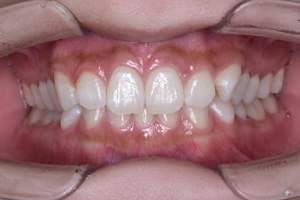

歯石除去

治療前

治療後

| 年齢 | 36歳・男性 |

| 主訴 | 歯石をとりたい |

| 治療内容 | 歯石除去 |

| 治療期間 | 30分 |

| 費用 | 約2,000円 |

| リスク・副作用 | ・歯ぐきの炎症が強いと歯石を取る際に出血することがあります。 ・処置後に歯がしみることがあります。 ・歯と歯の間に隙間ができるので、息が漏れ発音しにくいと感じることがあります。 ・歯ぐきの炎症が軽減すると歯ぐきが引き締まり、歯が長く見えることがあります。 |